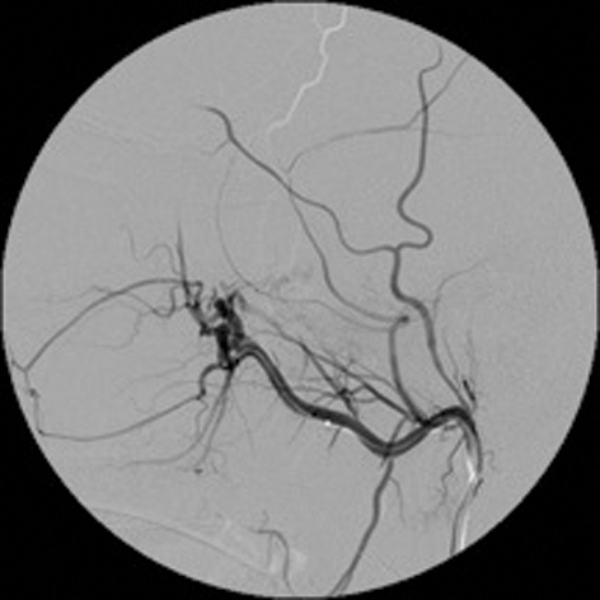

Embolisation is very effective in minimising intraoperative blood loss and is now a well-accepted part of the treatment of JNA [2]. (Figure 1 shows a case of preoperative embolisation of a juvenile angiofibroma).

Figure 1: Juvenile angiofibroma before and after embolisation.